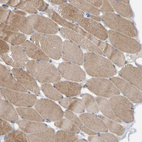

Immunohistochemistry analysis in human lymph node and pancreas tissues using HPA021669 antibody. Corresponding CCM2 RNA-seq data are presented for the same tissues.